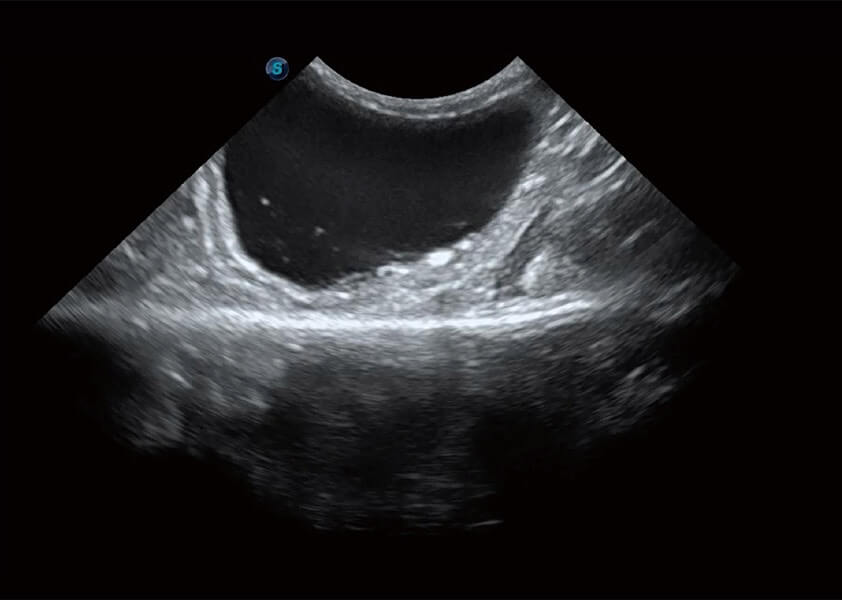

ProPet 60 作为一款高端台式动物超声设备,为动物医生的日常诊断提供了一系列贴合动物临床需求、解决临床实际问题的高级成像功能。凭借全系列高清探头,满足医生对腹部、心脏、生殖、浅表、肌骨等成像的所有需求,切实帮助您提升检查效率,提高诊断信心。

ProPet 60 尊享版

兽用彩色多普勒超声诊断系统